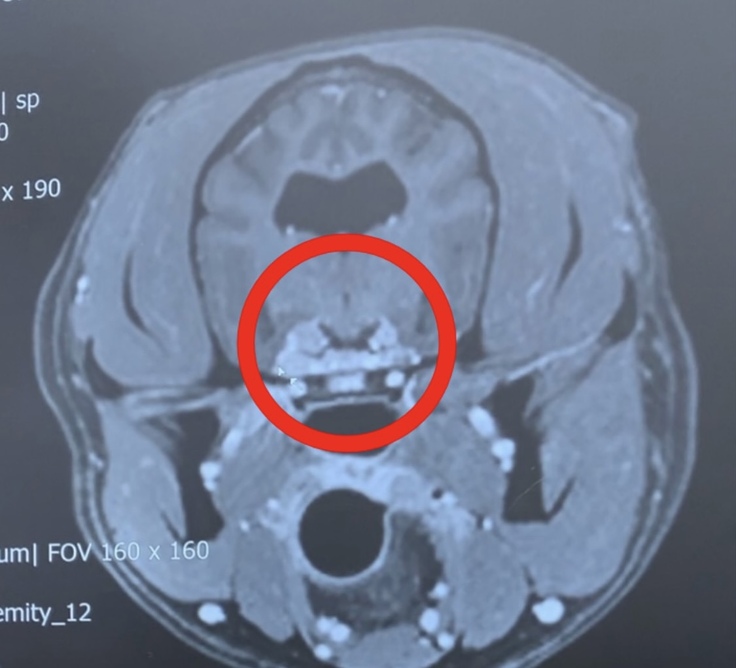

↑こちらの写真は、MRI画像です。

〇印をつけてある所がシャンティを苦しめている脳腫瘍です。

三叉神経・動眼神経です。

向かって右側よりも左側の方が大きい。

そして、とても小さいけど右側も腫瘍があると診断を受けています。